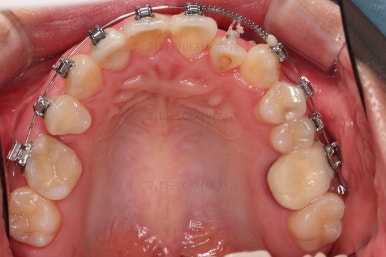

부산치과교정 키다리아저씨치과 초진 시 입안의 모습입니다.

확연히 좌우의 삐뚤어진 정도가 차이나죠.

덧니도 좌측(사진에서 보면 오른쪽) 위아래만 있는 상태고요.

좌측으로 삐뚤어져서 앞니도 좌측으로 쏠려 있는 상태였습니다.

부산치과교정 전후사진을 비교해 볼게요.

발치교정이라고 입매가 들어간 것도 아니고 오히려 더 예뻐졌죠?

중심선도 원하시는만큼 갖추었고, 가지런한 느낌도 좋고요.

21개월만에 전반적으로 매우 만족할만한 치료 결과를 얻었습니다.